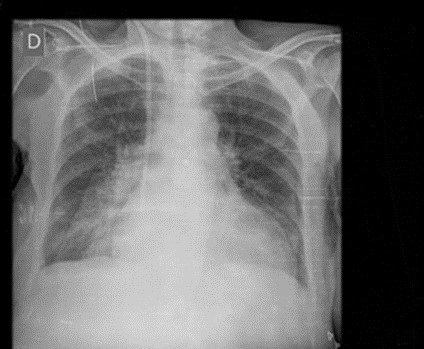

Regarding the recognition and removal of burned information present on the pixel data, here too the results were excellent for DX, CR and MG modalities with removal of all personal patient information. (See Fig.6) For other modalities (e.g., CT) the keras-ocr algorithms did not work very well because some pixel intensities variations were misinterpreted as text.

Figure 6: Image with sensible information burned

Figure 7: Image after the removing burned information